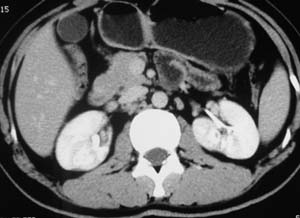

以下是引用子期在2010-3-19 20:47:00的发言:[br]血管畸形的ct增强应该有明显强化,本例并不相符合。本例双肾局部的略低密度影,累及肾盂,局部皮质明显变薄、内陷,增强扫描有轻度的强化,应考虑为炎性病变,患者为年轻男性,累及双肾的感染以结核较常见,可以没有明显的临床症状,尿中有时候也并不能查出什么;肾脓肿常有明显感染中毒症状,本例不符,另外一般的肾盂肾炎或肾小球肾炎通过小便就可确诊,其它还不能排除的是黄色肉芽肿性肾盂肾炎,然而单凭ct一般也很难鉴别。